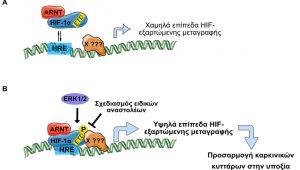

Τίτλος Ερευνητικού Έργου: Νέες πρωτεϊνικές αλληλεπιδράσεις του HIF-1α και ο ρόλος τους στην προσαρμογή των καρκινικών κυττάρων στην έλλειψη οξυγόνου

Επιστημονικός Υπεύθυνος: Μυλωνής Ηλίας